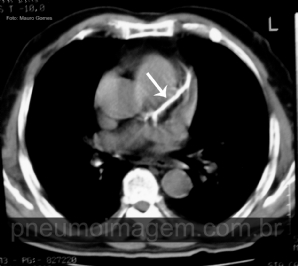

CASO CLÍNICO #28

Aproveitando o clima natalino, o caso desse mês mostra um sinal tomográfico interessante. Qual o nome desse sinal e o que ele significa? Deixe os seus comentários abaixo. ***** Enjoying the Christmas season, the case of this month shows an interesting to...